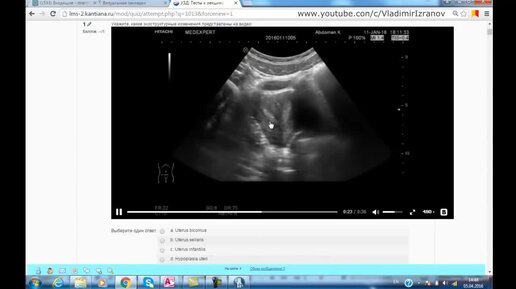

Анализ тестов к лекциям _Эхосемиотика структурных изменений органов малого таза_ (Часть 1)